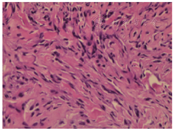

患者女性,26岁,因"左耳肿痛4个月余"于2018年11月4日来广州市增城区人民医院耳鼻喉科就诊并收入院。患者4个月前无明显诱因出现左耳肿痛,无发热,无耳流脓、听力下降、耳鸣,无眼睑闭合不全,无眩晕,曾就诊予头孢类药物治疗,耳痛症状好转,耳廓肿胀无法消退,近4个月来左耳肿胀隆起进行性加重,无伴疼痛,拟"左耳肿物性质待查"收入院。患者既往史无特殊,无疫区疫水及传染病接触史,否认肿瘤家族史。入院时专科体格检查:左耳廓背面、耳后沟前上方新生物,约1.0 cm×0.5 cm,表面光滑,边界清,质稍硬,活动度差,无明显压痛。新生物下方另见一孤立绿豆大小结节,表面光滑,性质同上,无压痛,耳廓表面皮肤未见破损及皮疹,余检查未见异常。入院后完善常规检查未见异常,颞骨薄层CT提示:左侧耳廓上方结节,边界尚清晰,无邻近组织侵犯表现(图1)。术前诊断为左耳肿物,于11月5日在局麻下行耳廓肿物切除,术中所见耳廓肿物边缘尚清晰,未见包膜包裹,与周围组织粘连,底部紧贴耳廓软骨,充分分离后完整切除肿物,耳廓软骨完整无破坏,分层缝合术腔加压包扎,肿物送病理检查。患者术后恢复情况良好,术后第2天出院。病理结果回报:(左耳廓肿物符合炎性肌纤维母细胞瘤(图2)。术后1周患者返院复诊见伤口愈合良好,局部拆线,告知患者病理结果并嘱其定期随诊。现患者术后随访14个月,无肿瘤复发表现,耳廓局部除轻微瘢痕形成外无明显异常。

根据肿瘤中(肌)纤维母细胞、炎性细胞分布和间质特征,IMT可大致分为3种组织学类型:①结节性筋膜炎样型,表现为梭形纤维母细胞或肌纤维母细胞松弛排列,伴浆细胞、淋巴细胞、嗜酸性粒细胞浸润,类似炎性肉芽肿;②纤维组织细胞瘤样型,表现为黏液样或胶原化背景下,梭形(肌)纤维母细胞围绕血管成束增殖,伴组织细胞样细胞浸润;③纤维瘤病样型:肿瘤细胞稀少,富含胶原及陈旧性瘢痕组织,炎症细胞浸润不明显[15]。文献报道[13,16],在免疫组化染色中,波形蛋白(vimentin)、平滑肌肌动蛋白(smooth muscle actin,SMA)、肌肉特异性肌动蛋白(muscle-specific actin)的阳性率分别达99%、92%及89%,此外,肌间线蛋白(desmin)和细胞角蛋白(cytokeratin)阳性率也分别为69%和36%。近年来,研究发现约50%的IMT患者存在间变性淋巴瘤激酶(anaplastic lymphoma kinase, ALK)基因重排和异常表达[17]。由于ALK蛋白异常表达及活性异常增强,可激活Ras-ERK、JAK-STAT、PI3K-Akt和PLC γ等多个与细胞增殖、存活、细胞骨架重排和细胞迁移等功能相关的信号转导通路,继而诱发肌纤维母细胞异常增殖,导致肿瘤发生[18]。此外,一些IMT患者虽然ALK检测阴性,但却证实了存在其他基因异常,如TFG-ROS1融合基因、ETV6基因重排和ETV6-NTRK3融合基因,证实了IMT为独立的肿瘤[19]。本病例报告中,手术切除标本镜下可见丰富梭形细胞及炎性细胞浸润,未见明显细胞异型性及核分裂象,可与恶性肿瘤细胞相鉴别,其镜下特点符合结节性筋膜炎样型IMT的组织学特征,免疫组化染色结果部分标志物符合IMT病变。